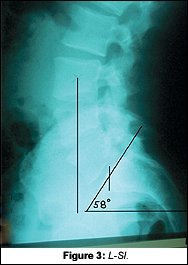

On Tony's x-rays, there were many subtle findings, but the lateral L-S showed more than enough reason for his 10 years of problems. A normal sacral base angle (Figure 2 on page NE-2) would be 36Á-42.Á Tony's lateral L-S (Figure 3) had a 56Á sacral base angle. In addition to this distortion, he also had a severe anterior gravity line. Normal weightbearing should bisect the anterior third of the sacral base.

The new x-rays showed significant changes to the neck and low back. The most obvious and most important was the change on the lateral L-S. Tony's sacral base angle went from 56Á to 46Á (Fig. 5). Knowing that normal is 36Á-42Á, this improvement was tremendous. Tony demonstrated many improved findings on his functional re-examination as well.